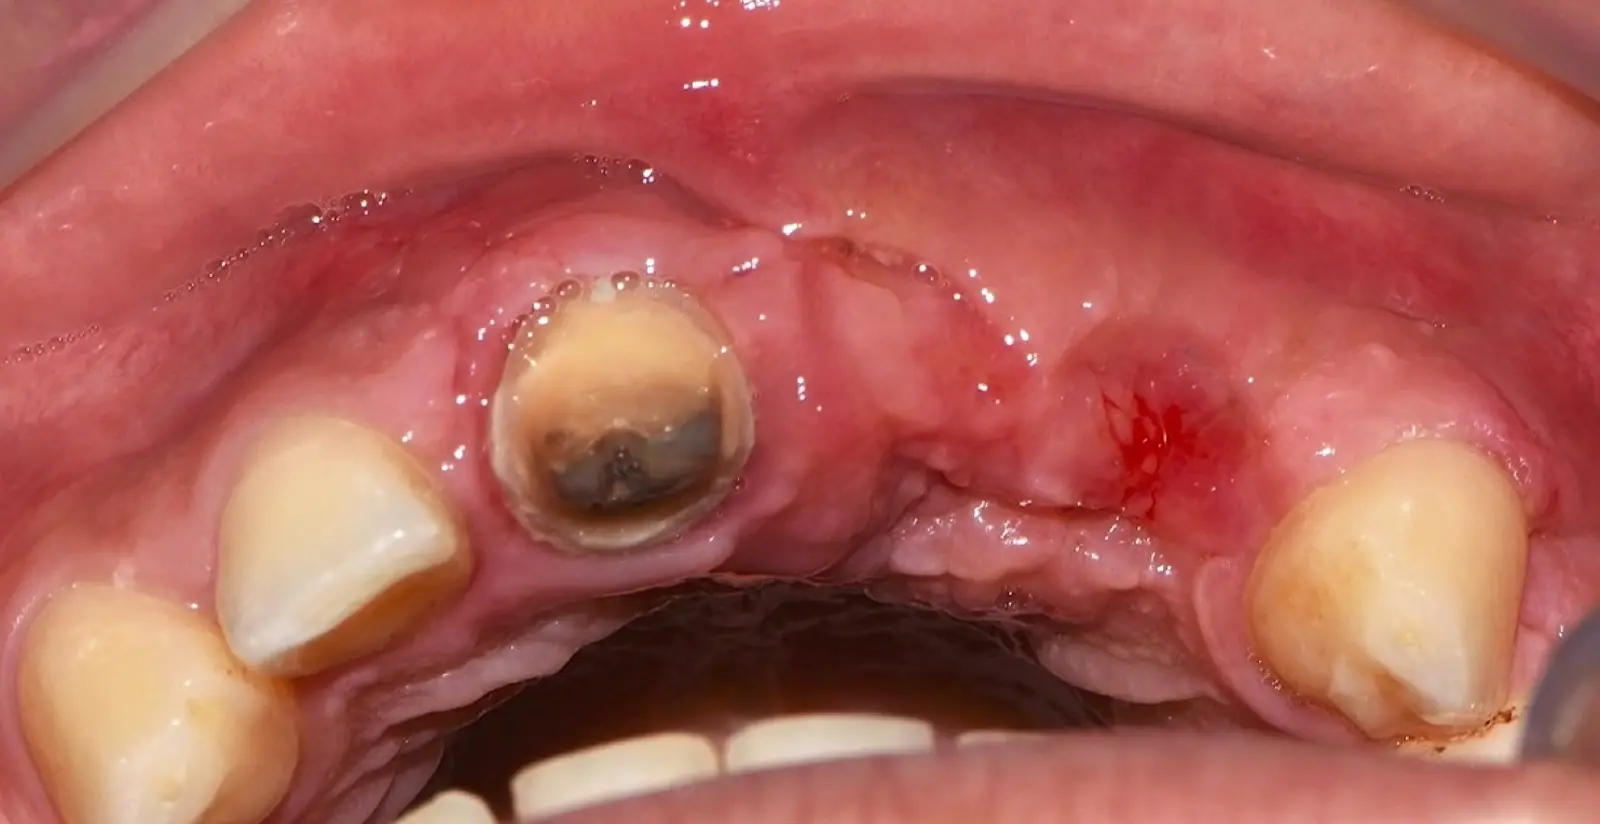

Figura 46. Control a los 10 días post cirugía.